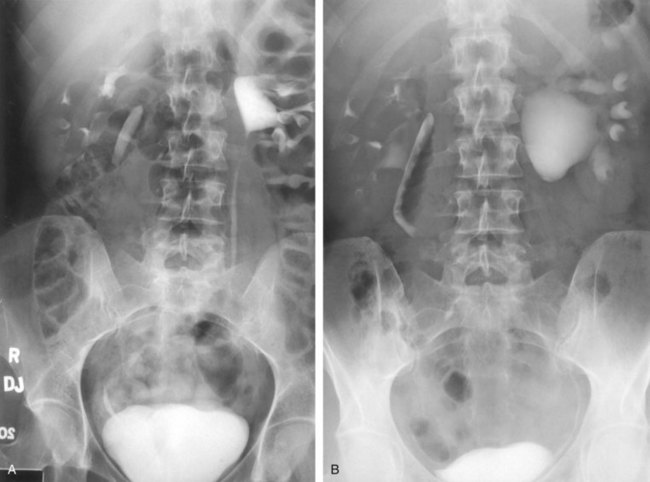

UPJ obstruction, although most often a congenital problem, can present clinically at any time of life. Historically, the most common presentation in neonates and infants was the finding of a palpable flank mass. However, the current widespread use of maternal, prenatal ultrasonography has led to a dramatic increase in the number of asymptomatic newborns being diagnosed with hydronephrosis, many of whom are subsequently found to have UPJ obstruction (Bernstein et al, 1988; Wolpert et al, 1989). A fraction of cases may also be found during evaluation of azotemia, which may result from bilateral obstruction in a functionally or anatomically solitary kidney. UPJ obstruction may also be incidentally found during studies performed to evaluate unrelated anomalies such as congenital heart disease (Roth and Gonzales, 1983). In older children or adults, intermittent abdominal or flank pain, at times associated with nausea or vomiting, is a frequent presenting symptom. Hematuria, either spontaneous or associated with otherwise relatively minor trauma, may also be an initial symptom. Laboratory findings of microhematuria, pyuria, or frank urinary tract infection might also bring an otherwise asymptomatic patient to the urologist. Rarely, hypertension may be a presenting finding (Riehle and Vaughan, 1981). Radiographic studies should be performed with a goal of determining both the anatomic site and the functional significance of an apparent obstruction. Although excretory urography remains a reasonable option for radiographic diagnosis, this study is less commonly used today. Classically, excretory urographic findings include delay in function associated with a dilated pelvicalyceal system. If the ureter is visualized, it should be of normal caliber. In some patients, symptoms may be intermittent and urography between painful episodes may be normal. In such cases the study should be repeated during an acute episode when the patient is symptomatic (Nesbit, 1956). Provocative testing with diuretic urography may allow accurate diagnosis in select cases. The patient should be well hydrated and the study then performed after injecting furosemide, 0.3 to 0.5 mg/kg (Malek, 1983) (Fig. 41–2).

Figure 41–2 A, This patient with intermittent left flank pain underwent intravenous urography. The calyces are sharp bilaterally without evidence of obstruction. However, there is a “box-shaped” pelvis on the left side, which may be associated with intermittent obstruction. B, This intravenous urogram in the same patient was performed along with injection of intravenous furosemide, which brought out the obvious left-sided ureteropelvic junction obstruction. The patient’s symptoms were subsequently relieved with a left pyeloplasty.